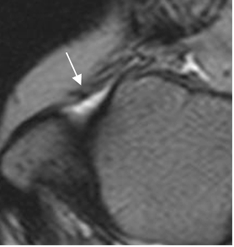

En los esguinces agudos grado I, se encuentra el ligamento íntegro, rodeado por líquido por edema o hemorragia y pérdida de los planos grasos. (Fig 60). En los grado II, el ligamento es irregular e hiperintenso, con cambios inflamatorios mas severos. (1, 12). (Fig 61, 62 y 63).

Fig 60. Esguince grado I.

RM axial en T2. Cambios inflamatorios rodeando el LPAA, el cual permanece intacto.